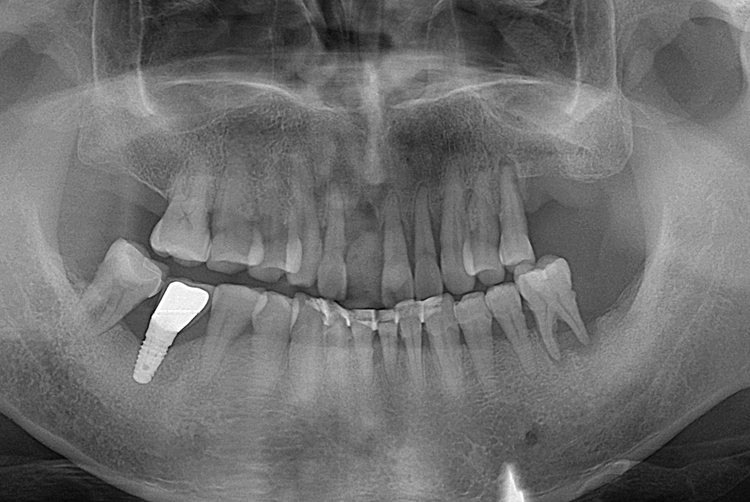

[임플란트] 앞니 임플란트

치료전 : 2018-07-11

치료후 : 2018-09-21

세종치과는 많은 환자와 다양한 케이스를 바탕으로

항상 편안한 임플란트 수술을 제공하고자 노력하고,

오래동안 튼튼히 쓸 수 있는 임플란트 수술을 가장 큰 목표로 삼고 있습니다.